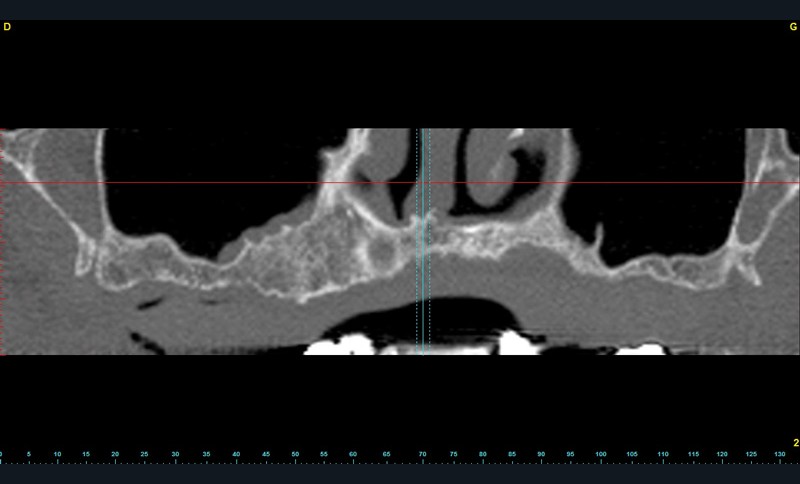

Un Dentascan® permet d’évaluer le volume osseux disponible pour une réhabilitation implanto-portée en complément de la radio panoramique de première intention. Cet examen confirme l’atrophie osseuse maxillaire (fig. 1 et 2).

En conséquence, une solution implantaire passe nécessairement par une reconstruction osseuse préalable. Une sur-élévation bilatérale des planchers sinusiens est réalisée avec un abord latéral. Les comblements des zones sous-sinusiennes sont effectués au moyen d’os allogénique (Maxgraft®) mélangé à un coagulum veineux prélevé en début d’intervention puis recouvert d’une membrane de collagène Bio-gide® et de PRF’s. La prothèse totale est évidée et rebasée périodiquement avec une résine souple.